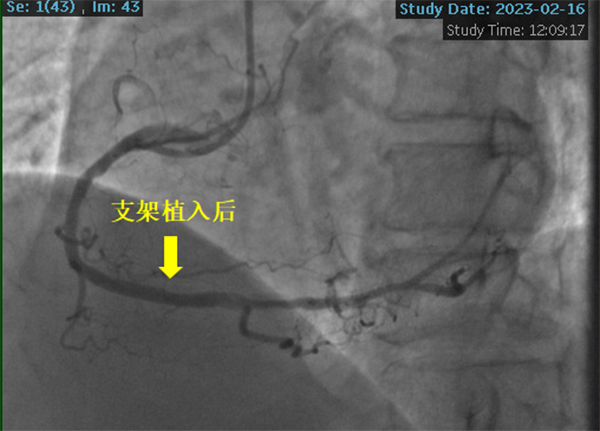

2023年2月16日,在副院長楊煜的統(tǒng)籌指導下,心內(nèi)科冠脈專業(yè)專家組夏勇主任、徐通達主任、錢文浩主任、徐晤主任、陸遠主任等針對病例進行了充分的討論及術(shù)前準備,由潘德鋒主任進行手術(shù)操作。術(shù)中首先利用血管內(nèi)超聲明確患者冠狀動脈的鈣化情況及血管直徑,在血管內(nèi)超聲的指導下,選擇了4.0mm×12mm的沖擊波球囊,順利送入沖擊波球囊至鈣化病變部位,釋放脈沖,每次釋放10個脈沖,最終通過釋放80個脈沖,將鈣化斑塊進行了充分預處理,成功為患者植入了一枚冠脈支架,術(shù)后血管內(nèi)超聲顯示支架貼壁良好,患者癥狀明顯緩解,2月18日康復出院。

沖擊波球囊技術(shù)為冠脈鈣化病變的治療提供了一種全新選擇和有力“武器”,被稱為冠脈鈣化病變的“終結(jié)者”,國內(nèi)于2021年7月開展第一例,本次超聲波球囊技術(shù)的開展為淮海經(jīng)濟區(qū)公立醫(yī)院首例。沖擊波球囊技術(shù)的成功開展標志著徐州醫(yī)科大學附屬醫(yī)院冠心病復雜病變診治水平的進一步提高,該患者的成功救治充分體現(xiàn)了徐醫(yī)附院疑難急危重癥患者的救治水平和多學科協(xié)作能力,一方面充分反映了本院神經(jīng)內(nèi)科ICU針對重癥患者的救治水平,另一方面體現(xiàn)了徐醫(yī)附院心臟團隊針對復雜高危冠脈病變的診療規(guī)范性及技術(shù)能力。在醫(yī)院高質(zhì)量轉(zhuǎn)型發(fā)展的過程中,心內(nèi)科將立足學科發(fā)展,緊跟國內(nèi)外先進技術(shù),進一步推進冠心病的介入治療,為廣大淮海地區(qū)的冠心病患者保駕護航。